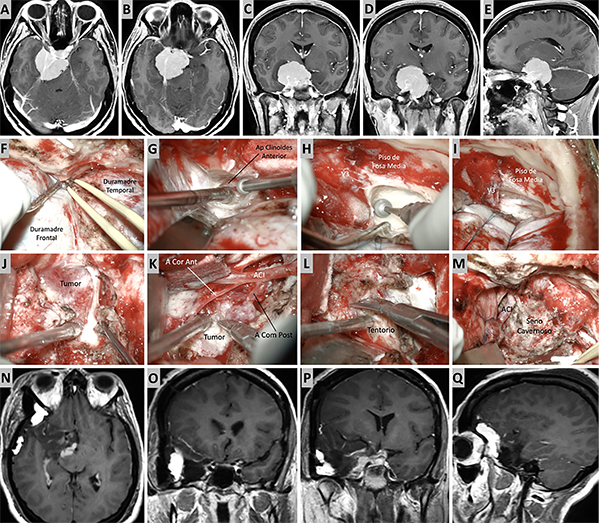

Figura 11. Caso ilustrativo #9. A-D. Imagen por RMN que muestran MRPC con implantación petroclival, extensión a la fosa craneal media y clinoides anterior. F-L. Se realizo un abordaje combinado con clinoidectomia anterior extradural y petrosectomia anterior. N-Q. Se consiguió una resección casi total. Imágenes postquirúrgica por RMN.